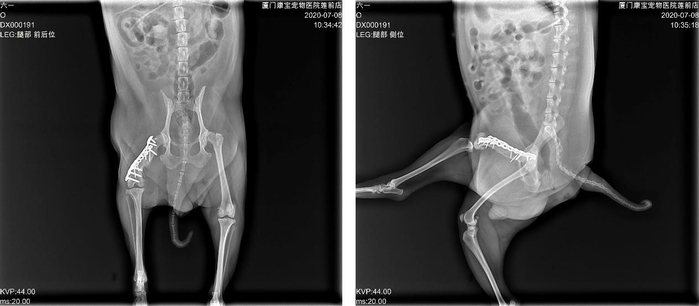

首先做X线片检查,发现双后肢髋关节均有退行性关节病变,右后肢股骨中断骨折,股骨长度与左侧对比明显缩短,断端萎缩,骨骼密度明显下降,骨髓腔不明显,骨折处残留一处环扎钢丝,大腿外侧瘘道分泌物细胞学显示化脓性炎症及胞内球菌。

后期的恢复还算顺利,伤口一期愈合,术后一周就开始用患肢点地了,之后每月复查。6个月后,可以观察到骨折断端基本愈合,能用患肢正常走路。